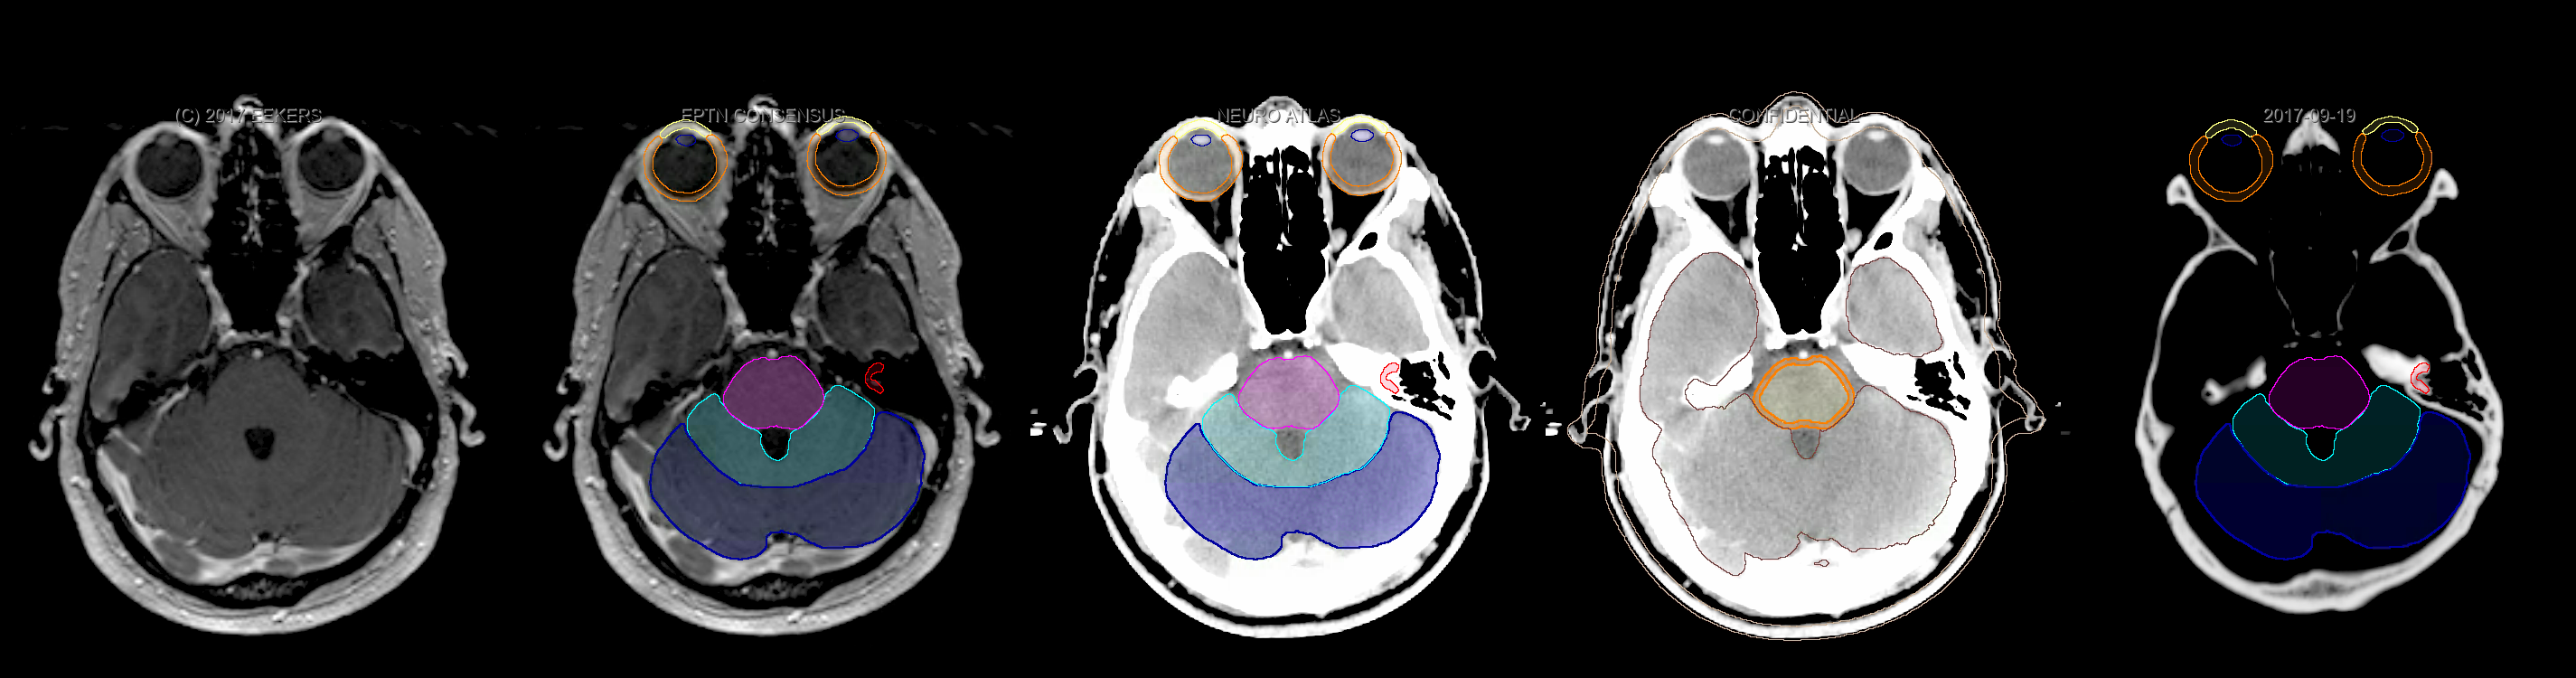

Eekers et al. have published an international neurological atlas for contouring of organs at risk in consensus with the European Particle Therapy Network (EPTN). The purpose of this consensus atlas is to decrease inter- and intra-observer variability in delineating OARs relevant for neuro-oncology. We propose this atlas is used in photon and particle therapy in order to derive consistent dosimetric data. When required this atlas will be updated according to new insights.

Included are all OARs known to be relevant for radiation-induced toxicity in neuro-oncology: brain, brainstem, cochlea, vestibulum & semicircular canals, cornea, lens, retina, lacrimal gland, optic nerve, chiasm, pituitary, hippocampus and skin. A new OAR relevant for neuro-cognition, the posterior cerebellum is also included.

Three-dimensional delineation of the fifteen consensus OARs for neuro-oncology are shown on CT and 3 Tesla (3T) MR images (slice thickness 1 mm with intravenous contrast agent). All are presented in transversal, sagittal and coronal view.

From left to right: MR without structures, MR with structures, CT (WW/WL 120/40) with structures, CT (WW/WL 120/40) with Brain and Brainstem Surface, CT (WW/WL 1500/120)with structures